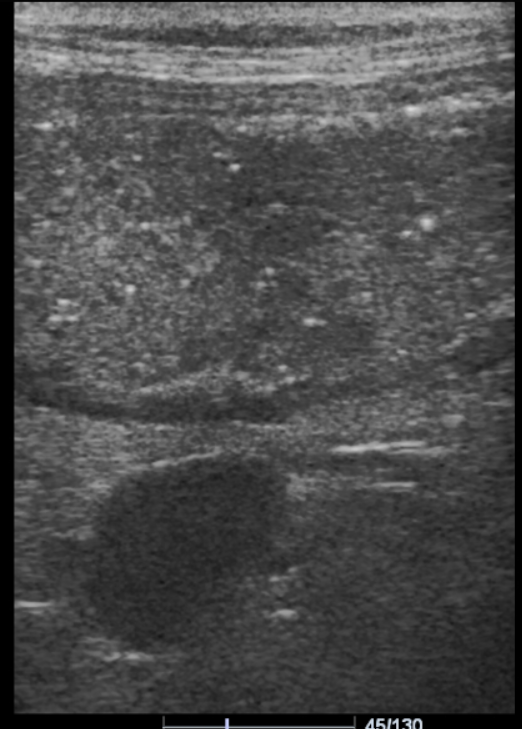

Диагностика. По результатам УЗИ выявлены дилатированные содержимым и пневматизированные петли тонкого и толстого кишечника, перистальтика сохранена и местами усилена (рис. 2). Такая картина характерна для нарушения усвоения питательных веществ в кишечнике и избыточного бактериального роста.